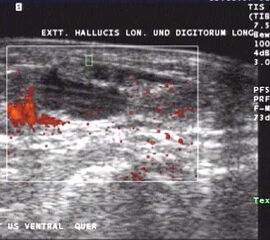

Sonographie

Die sonographische Untersuchung des Fußes wird in der Regel mit 7,5MHz durchgeführt. Erfasst und differenziert werden können ein Gelenkerguss bei Synovialitis, eine Bursitis bzw. eine Tenosynovialitis. Mit Hilfe des Power-Dopplers kann auch eine Aussage über die Krankheitsaktivität gemacht werden.

Flüssigkeit und erhöhte Gewebeperfusion im Powerdoppler sind Kennzeichen der rheumatoiden Arthritis im Ultraschall. Hier zeigt sich die Entzündung um die Extensor hallucis longus Sehne.

Abbildung 3